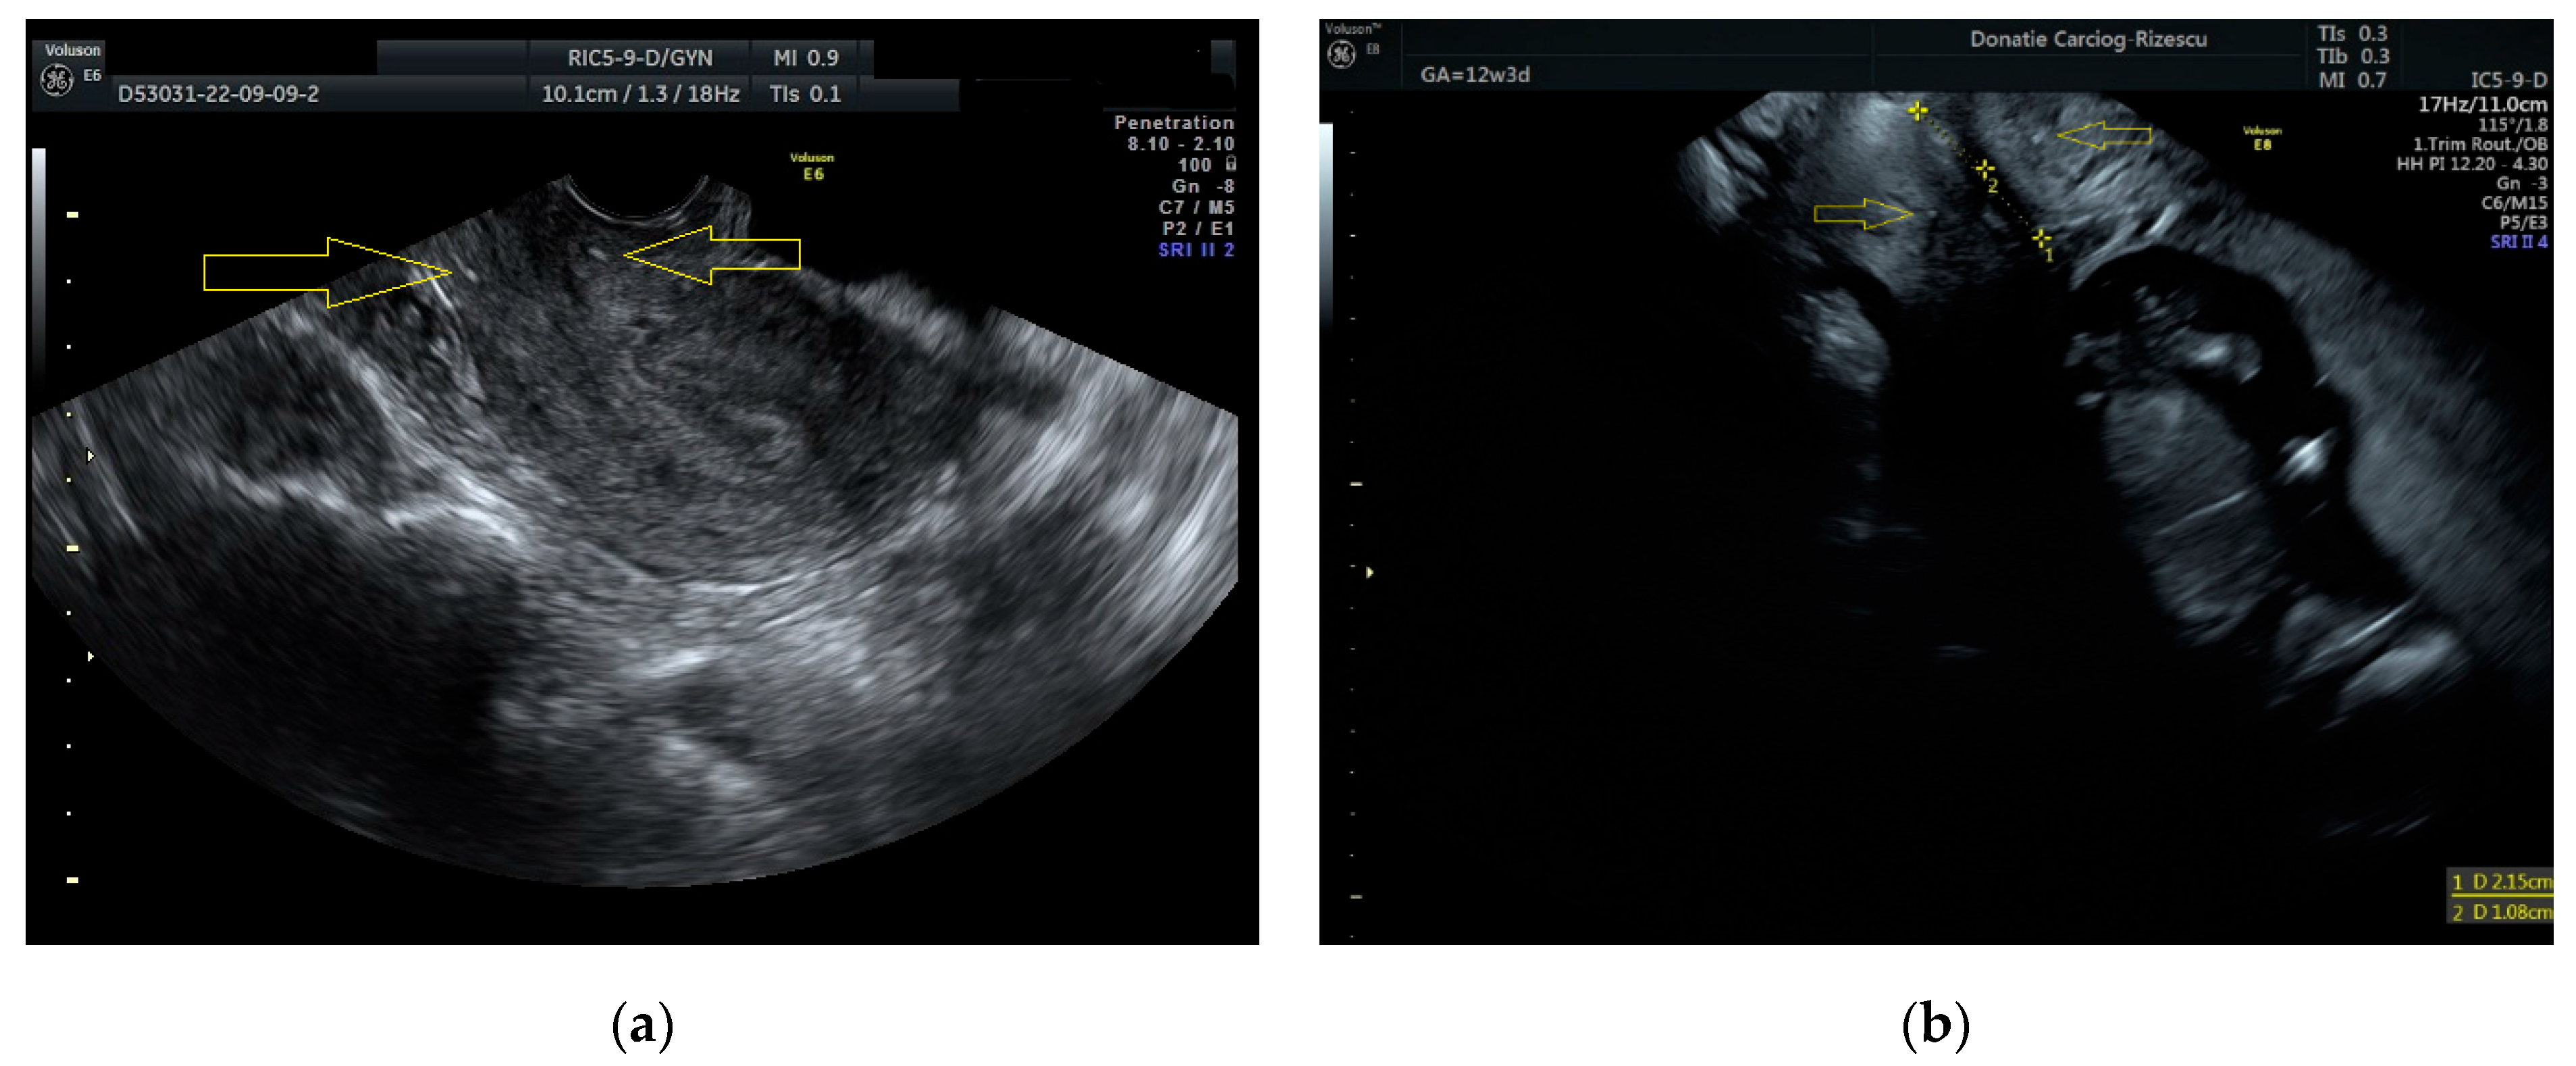

| Cervical length (mm) | 28 | 21.5 | 22.6 | |

| Cerclage thread—internal ostium distance (mm) | NA | 10.7 | 10.1 | |

| Cerclage thread—external ostium distance (mm) | NA | 10.8 | 12.5 | |